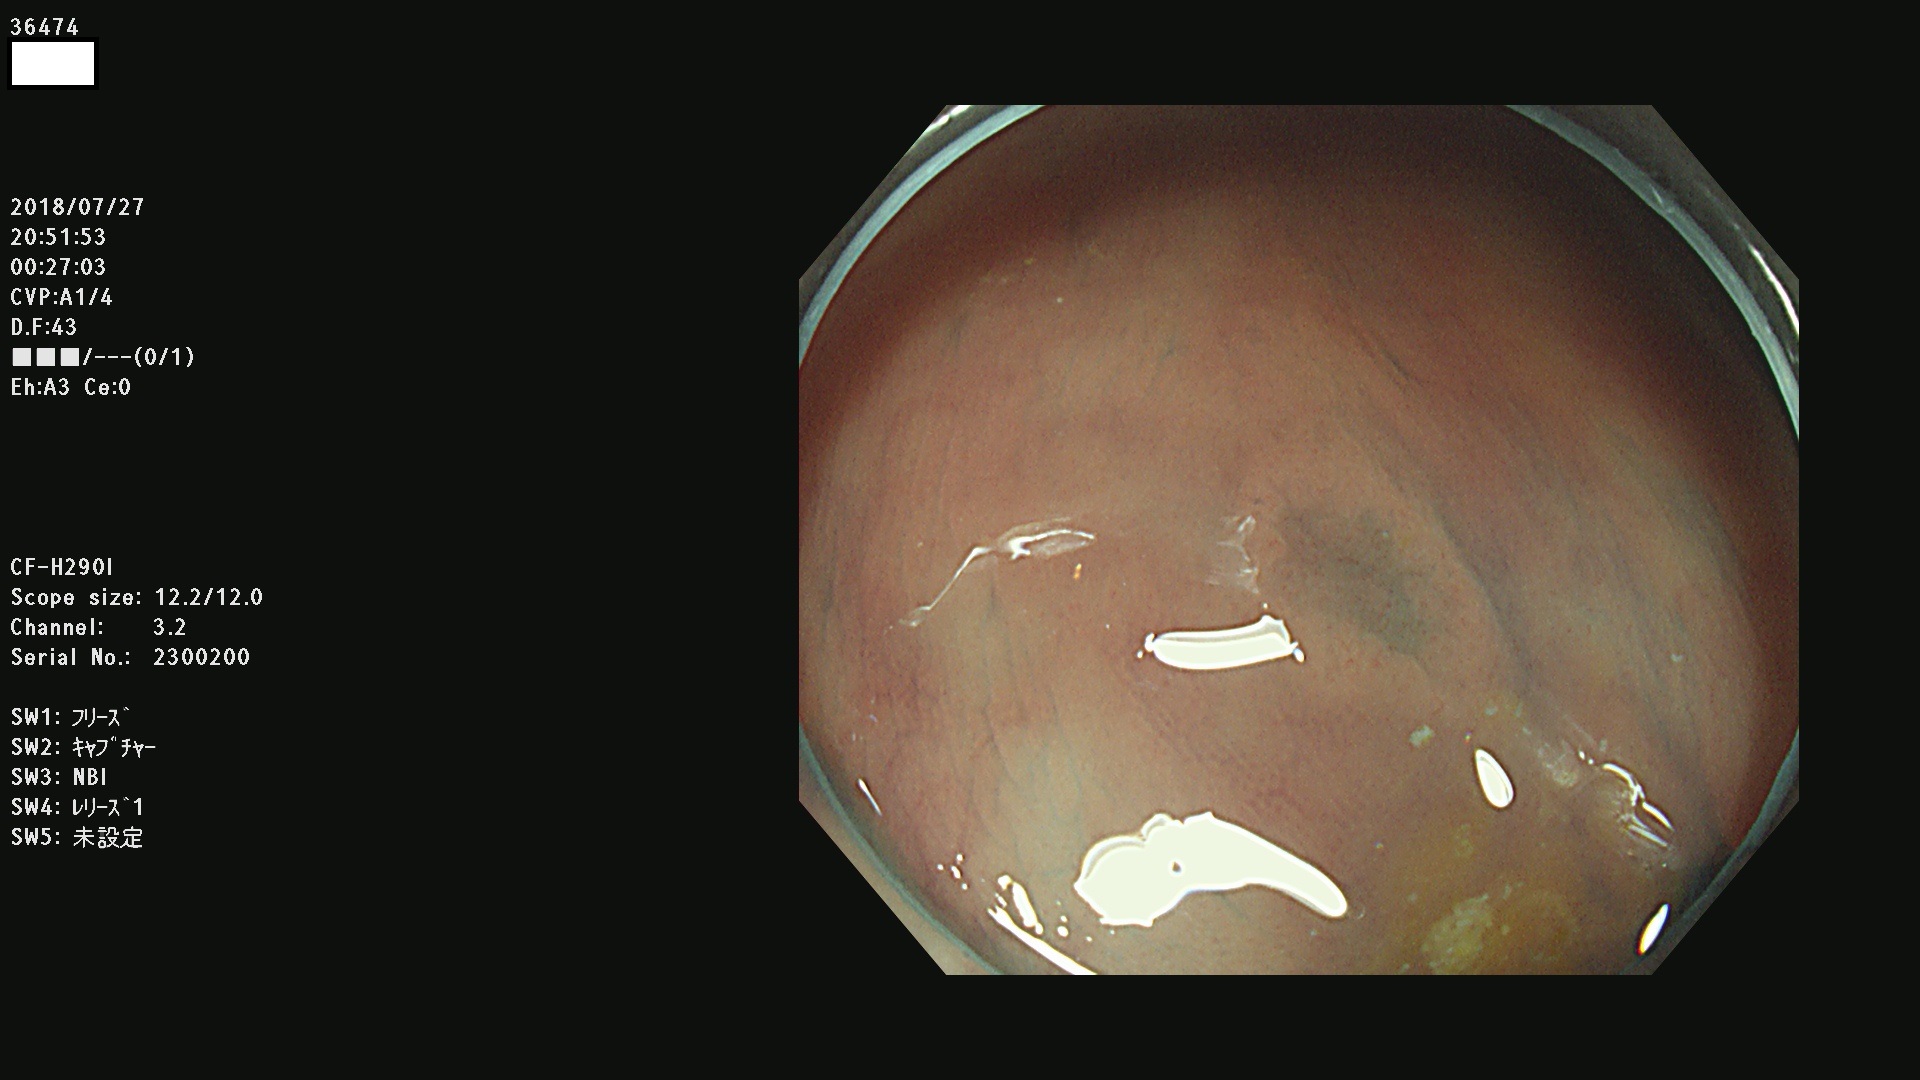

36400(SSAPのみ) 36402 36403 36404 36405 36406 36407 36408(SSAPのみ) 36412 36413 36414 36415 36416 36417 36418 36420 36422 36423 36424 36425 36426 36428 36429 36430 36431 36434 36435 36436 36437 36438 36440 36443 36447 36448 36449 36450 36452 36454 36458 36459 36460 36462(SSAPのみ) 36463 36464 36465 36466 36470 36471 36472 36473 36474 36475 36476 36478 36480 36481 36482 36484 36487 36488 36489 36490 36492 36494 36495 36496 36497 36498

発見困難で危険性の高い平坦型病変(上記100名より抽出)